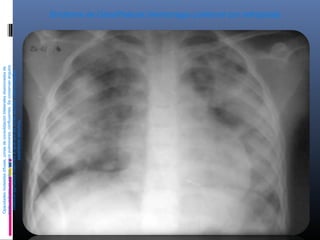

1. Edema pulmonar

 Extravasación anormal de líquido en el

tejido pulmonar

 Puede ser intersticial y/o alveolar.

 El fallo cardiaco izquierdo es la causa más

frecuente de edema pulmonar diseminado.

Cardiogénico

 Generalmente existe congestión vascular

pulmonar, como fase preedematosa en la

que las venas pulmonares están distendidas

y existe una redistribución del flujo

sanguíneo pulmonar, con distensión de las

ramas de los lóbulos inferiores, al contrario

de lo que sucede en el individuo normal.

 La congestión pulmonar se complica

primeramente con edema intersticial,

viéndose borrosidad de los vasos debido al

edema perivascular, más frecuentemente a

nivel de los hilios.

 La presencia de ingurgitación en los

espacios interlobulares produce la aparición

de edema septal, que se caracteriza

radiográficamente por la presencia de líneas

de Kerley.

 Infiltrado en

alas de

mariposa ó de

murciélago, por

edema

pulmonar.

 Líneas B de

Kerley.